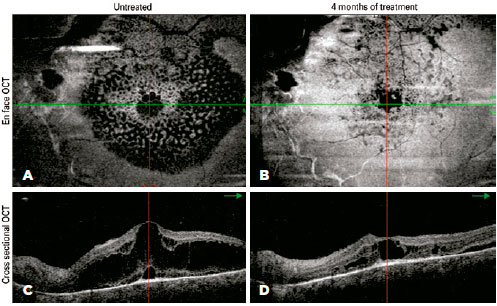

During the first four months of treatment, all patients experienced some anatomical improvement in hemangioma-related complications in the posterior segment (Figure 3). However, in the following three months, the steady sequential improvement was replaced by mild worsening and then clear anatomical worsening (Figure 4), which led to us stopping the β-blocker therapy. Compared with the beginning of treatment, there was no overall deterioration in visual acuity or aggravation of lesions. All patients continue to be followed up, and patients 3 and 4 will be offered alternative therapy if their visual acuities deteriorate.